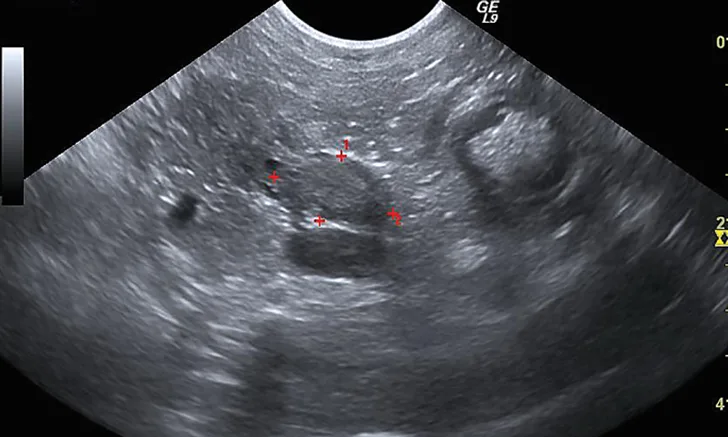

Figure 1 Sonographic image of the nodule at the base of the left lobe of the pancreas (outlined by red markers)

Additional diagnostics were pursued. Abdominal ultrasonography demonstrated an ill-defined and mildly hyperechoic 0.75 × 1.37-cm nodule at the base of the left lobe of the pancreas (Figure 1). Small, well-defined hyperechoic nodules were also found scattered throughout all liver lobes. Three-view thoracic radiographs revealed no significant abnormalities.